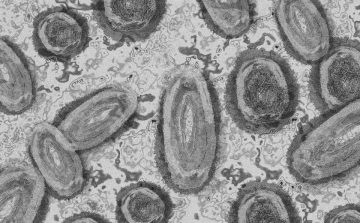

Tovább nőtt a majomhimlő-fertőzöttek száma Magyarországon

Újabb két embernél igazolt majomhimlő-fertőzést a Nemzeti Népegészségügyi Központ (NNK) a 33. héten - augusztus 15-től 21-ig -, ezzel 64-re nőtt a magyarországi esetek száma.

Egy 3 év alatti gyermek fertőződött meg majomhimlővel Belgiumban

Belgiumban egy 3 év alatti gyermek fertőződött meg majomhimlővel - számolt be róla szerdán a Sudinfo hírportál.

Megfertőződött a majomhimlővel egy gyerek Németországban

Megfertőződött majomhimlővel egy négyéves kislány Németországban - jelentették kedden német hírportálok az országos közegészségügyi intézet (RKI) adatai alapján.